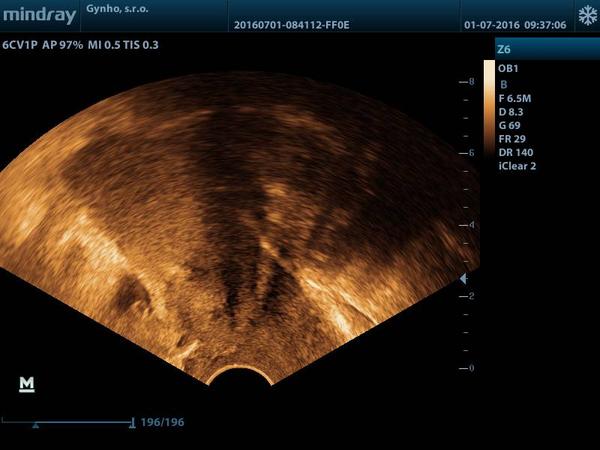

holky sem po ivf kde mi texl zavedl 2 embria dnes sem 9 tt foto je v 4 tt myslíte ze tam sou dve nebo jedno muj gyndar rikal ze vidi jen jedno ale ze je to velice brzo dekuji za radu

@barisej netroufnu si to posoudit. Dutinku vidim jednu, ale jestli je to uzv z 4tt je opravdu brzo. Ted jsi v 9tt to so tatim neměla delany uzv na průkaz srdeční akce?

@barisej Ve 4. týdnu z UTZ určitě jedno nebo dvě nezjistí, ale teď už musíš mít 100% srdeční akci a ta je buď jedna nebo dvě.